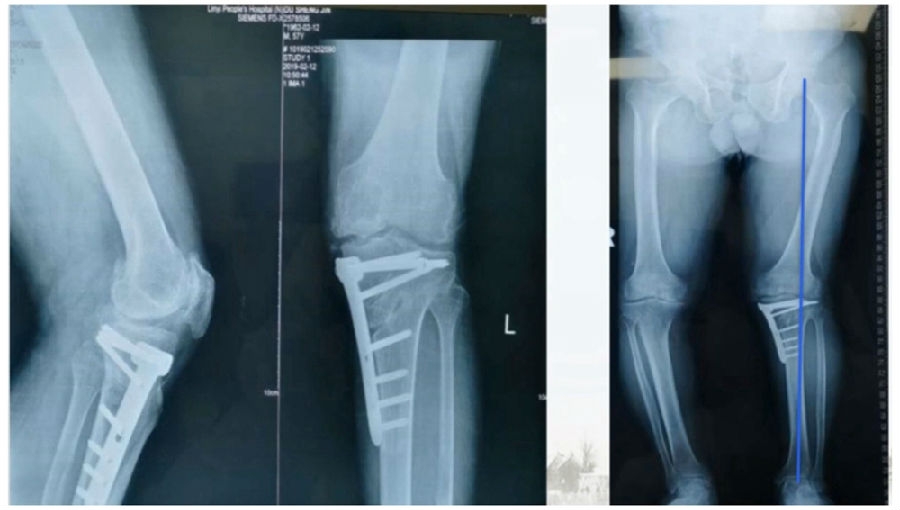

典型病例,男性,57岁,农民,左膝疼痛3年。

术前

术前影像资料

术中先打克氏针确定截骨方向,先做关节内截骨,截完后测量下肢力线,发现并没达到术前设计的Fujisawa点。

术中影像资料

随后用骨刀继续向前敲,做HTO内侧开放楔,截骨完成后内侧固定,并测量下肢力线,此时达到术前设计的要求。

该患者撑开较大,取了髂骨进行植骨。

最终力线

术后检查证实达到了术前预期的手术效果,关节线达到了平行,半脱位得到矫正,同时关节线和地面水平。病人行走达到了理想的效果。

术后X线

患者术后4个月截骨愈合,膝关节稳定维持得非常好。

术后4个月